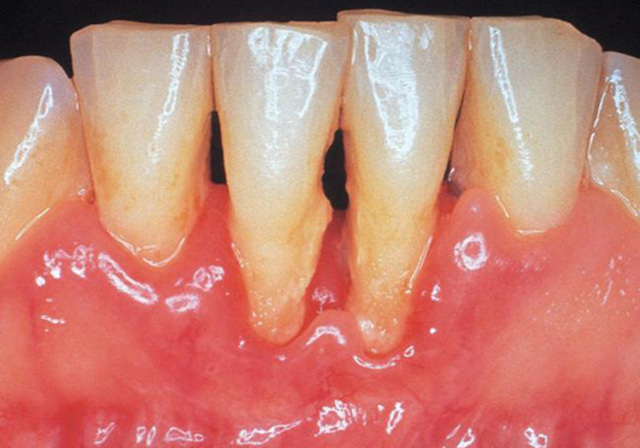

➤ Khi cao răng bình thường trở thành cao răng huyết thanh (màu đỏ), sức “công phá” của chúng sẽ lớn hơn rất nhiều. Lúc này, bạn sẽ phải đối mặt với các nguy cơ bệnh lý răng miệng nguy hiểm hơn rất nhiều lần như viêm nướu răng, viêm nha chu, tụt nướu chân răng, viêm tủy răng, tiêu xương răng…

➤ Cao răng màu đen là tình trạng báo động, nó hoàn toàn có thể cướp đi tất cả những chiếc răng trên khuôn hàm của bạn chỉ trong một thời gian ngắn. Cũng giống như cao răng huyết thanh, cao răng màu đen gây ra một loạt biến chứng nguy hiểm, thậm chí còn ảnh hưởng đến cả sức khỏe.

Cao răng làm sức đề kháng của cơ thể bị giảm sút và có thể làm trầm trọng hơn các bệnh về tim mạch hay tiểu đường.